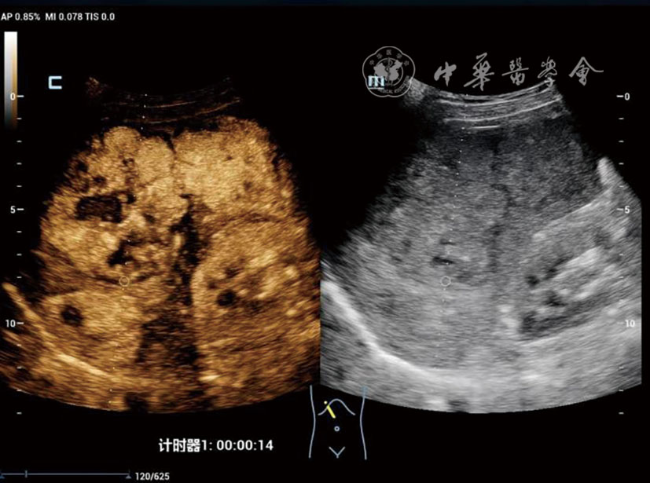

DPHCC组血清甲胎蛋白≥400 ng/ml的比例(48.4% vs 15.0%,P=0.002)及微血管浸润率(77.4% vs 17.5%,P<0.001)显著高于THCC组。超声造影显示,与THCC组相比,DPHCC组动脉期以不均匀增强(38.7% vs 15.0%)和环状增强(16.1% vs 2.5%)为主(P=0.003),且廓清时间更早[(91.94±37.58) s vs (131.65±59.71)s,P=0.002)]。多因素Logistic回归分析显示,肿瘤大小(OR=1.019,P=0.002)、甲胎蛋白≥400 ng/ml(OR=2.798,P=0.032)、边界不清(OR=3.204,P=0.020)及廓清时间<120 s(OR=2.221,P=0.049)是DPHCC的独立危险因素。

The DPHCC group showed significantly higher rates of serum alpha-fetoprotein (AFP) ≥400 ng/ml (48.4% vs 15.0%, P=0.002) and microvascular invasion (77.4% vs 17.5%, P<0.001) compared to THCC. On CEUS, DPHCC predominantly exhibited heterogeneous enhancement (38.7% vs 15.0%) and rim-like enhancement (16.1% vs 2.5%) in the arterial phase (P=0.003), with earlier contrast agent washout initiation (91.94±37.58 s vs 131.65±59.71 s, P=0.002). Multivariate analysis identified tumor size (odds ratio [OR]=1.019, P=0.002), AFP≥400 ng/ml (OR=2.798, P=0.032), ill-defined margin (OR=3.204, P=0.020), and washout time <120 s (OR=2.221, P=0.049) as independent risk factors for DPHCC.

表2 DPHCC组与THCC组患者的灰阶超声及超声造影特征比较[例(%)] |

增强时间(s,![]() | 15.32±4.37 | 16.88±4.88 | t=1.14 | 0.169 |

廓清时间(s,![]() | 91.94±37.58 | 131.65±59.71 | t=3.41 | 0.002 |

| 动脉期增强方式 | - | 0.003 | ||

| 均匀增强 | 14(45.2) | 33(82.5) | ||

| 不均匀增强 | 12(38.7) | 6(15.0) | ||

| 环状增强 | 5(16.1) | 1(2.5) | ||

| 门脉期增强程度 | - | 0.060 | ||

| 高增强 | 1(3.2) | 4(10.0) | ||

| 等增强 | 4(12.9) | 13(32.5) | ||

| 低增强 | 26(83.9) | 23(57.5) | ||

| 实质期增强程度 | - | 0.157 | ||

| 高增强 | 1(3.2) | 0(0) | ||

| 等增强 | 0(0) | 3(7.5) | ||

| 低增强 | 30(96.8) | 37(92.5) | ||

| 内部灌注缺损 | χ2=0.13 | 0.722 | ||

| 无 | 27(87.1) | 36(90.0) | ||

| 有 | 4(12.9) | 4(10.0) |

注:DPHCC为双表型肝细胞癌;THCC为经典型肝细胞癌;-表示Fisher检验无统计值 |